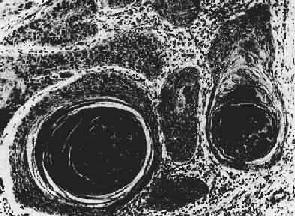

图7-13 腺癌(胃) 癌细胞排列紊乱,多层,形成大小不等、形状不规则的腺样结构,浸润于胃壁组织内 (2)粘液癌(mucoid carcinoma):又称为胶样癌(colloid carcinoma),常见于胃肠。镜下,初时粘液聚积在癌细胞内,将核挤向一侧,使该细胞成印戒状, 故一般称之为印戒细胞(signet-ring cell)。以后粘液堆积在腺腔内,并可由于腺体的崩解而形成粘液池。此时,往往可见于小堆或散在的印戒状癌细胞漂浮其中。肉眼观,癌组织呈灰白色,湿润,半透明如胶冻样,胶样癌因而得名。 (3)实性癌(solid carcinoma):或称单纯癌(carcinoma simplex),属低分化的腺癌,恶性程度较高,多发生于乳腺,少数可发生于胃及甲状腺。癌巢为实体性,无腺腔样结构,癌细胞异型性高,核分裂像多见。有的癌巢小而少,间质结缔组织多,质地硬,称为硬癌(scirrhous carcinoma)(图7-14)。有的则癌巢较大较多,间质结缔组织相对较少,质地如脑髓,称为髓样癌(medullary carcinoma)。

图7-14 乳腺硬癌 癌细胞呈条索状排列,间质丰富,由多量纤维组织构成